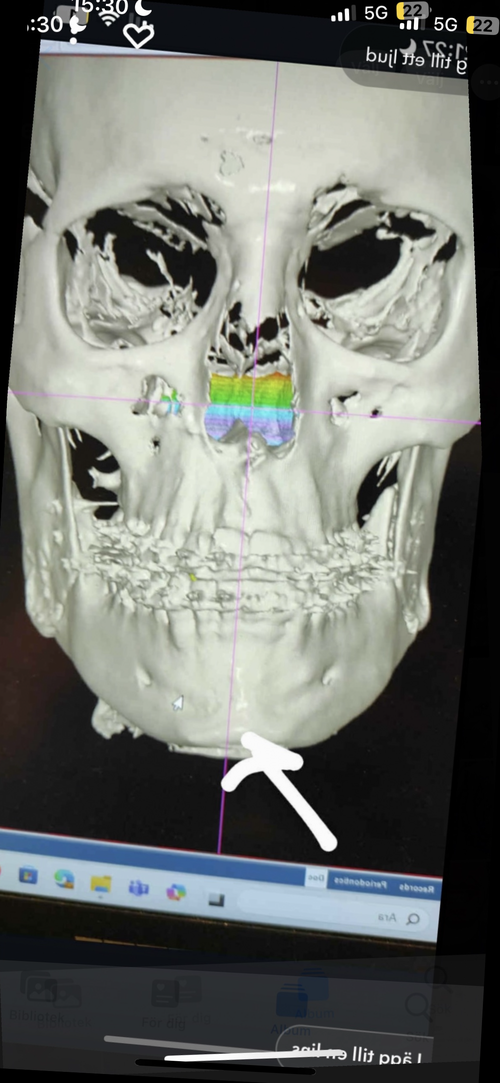

The proximal segment was torqued. Specifically, the external oblique ridge (upper ramus) was moved laterally, while the lower portion of the ramus, the gonial angle rotated inward (medially). This creates a mismatch. Increased width in the mid-ramus region, but reduced width and definition at the angles.

The circled area shows the external oblique ridge. Since the masseter attaches in this region, lateral displacement here combined with segment rotation can contribute to the inward positioning of the gonial angles and the overall distorted appearance.

Ps. Notice how my head tilt on the after cbct are totally off, that’s what happens when you do a unsymmetrical yaw rotation to correct asymmetry, how ironic. I needed to adjust the after cbct because my head leans 2-3 mm to the left now.

The proximal segment was torqued. Specifically, the external oblique ridge (upper ramus) was moved laterally, while the lower portion of the ramus, the gonial angle rotated inward (medially). This creates a mismatch. Increased width in the mid-ramus region, but reduced width and definition at the angles.

The circled area shows the external oblique ridge. Since the masseter attaches in this region, lateral displacement here combined with segment rotation can contribute to the inward positioning of the gonial angles and the overall distorted appearance.

Ps. Notice how my head tilt on the after cbct are totally off, that’s what happens when you do a unsymmetrical yaw rotation to correct asymmetry, how ironic. I needed to adjust the after cbct because my head leans 2-3 mm to the left now.